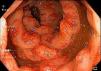

Los hallazgos descritos en la colonoscopia fueron: lesiones polipoideas, lesiones ulceradas y lesión tumoral (figs. 4 y 5a,b).

Los sitios más afectados fueron el colon transverso, el colon sigmoides y el recto (tabla 3) (figs. 6-9 y 10a,b).

En los pacientes a quienes se les realizó colonoscopia se reportaron lesiones polipoides en el 100% de los pacientes, lesiones ulceradas en el 40% y mucosa edematosa, así como lesión tumoral en el 20% de los pacientes; el colon transverso, el colon sigmoides y el recto se reportaron afectados en un 60% de los pacientes.